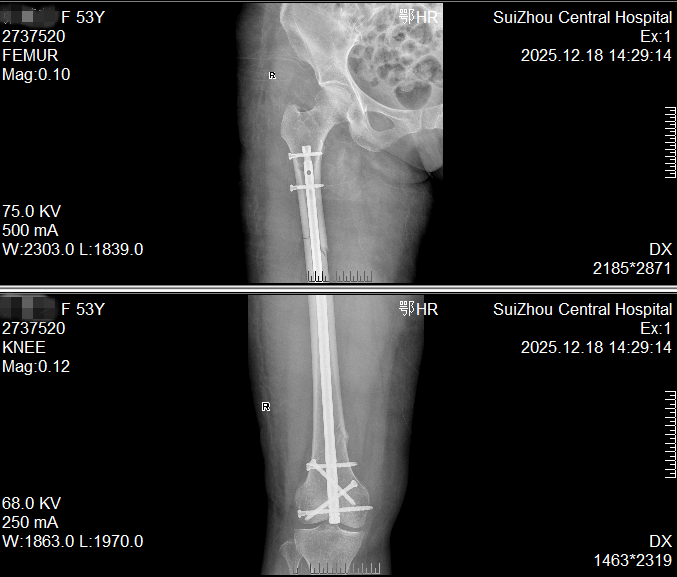

大腿多段骨折,一个小口完成修复

一位53女士大腿多处骨折,甚至影响到膝盖。我们仅在膝盖上方开一个约4厘米的小口,放入一根髓内钉将骨折处全部连接固定。这样既保护了腿部血流和肌肉,也为后期膝盖活动打下了好基础。